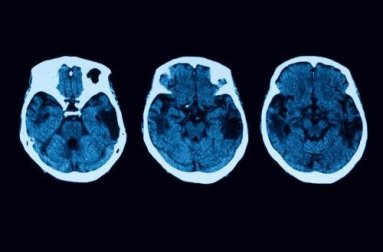

Ma gli esami utili a formulare la giusta diagnosi non si fermano qui. Per togliere ogni dubbio, verranno eseguiti degli esami neurologici, tra cui risonanze magnetiche e tomografie. Se tutto porta a un caso di atrofia corticale posteriore, allora il paziente può optare per diversi trattamenti.